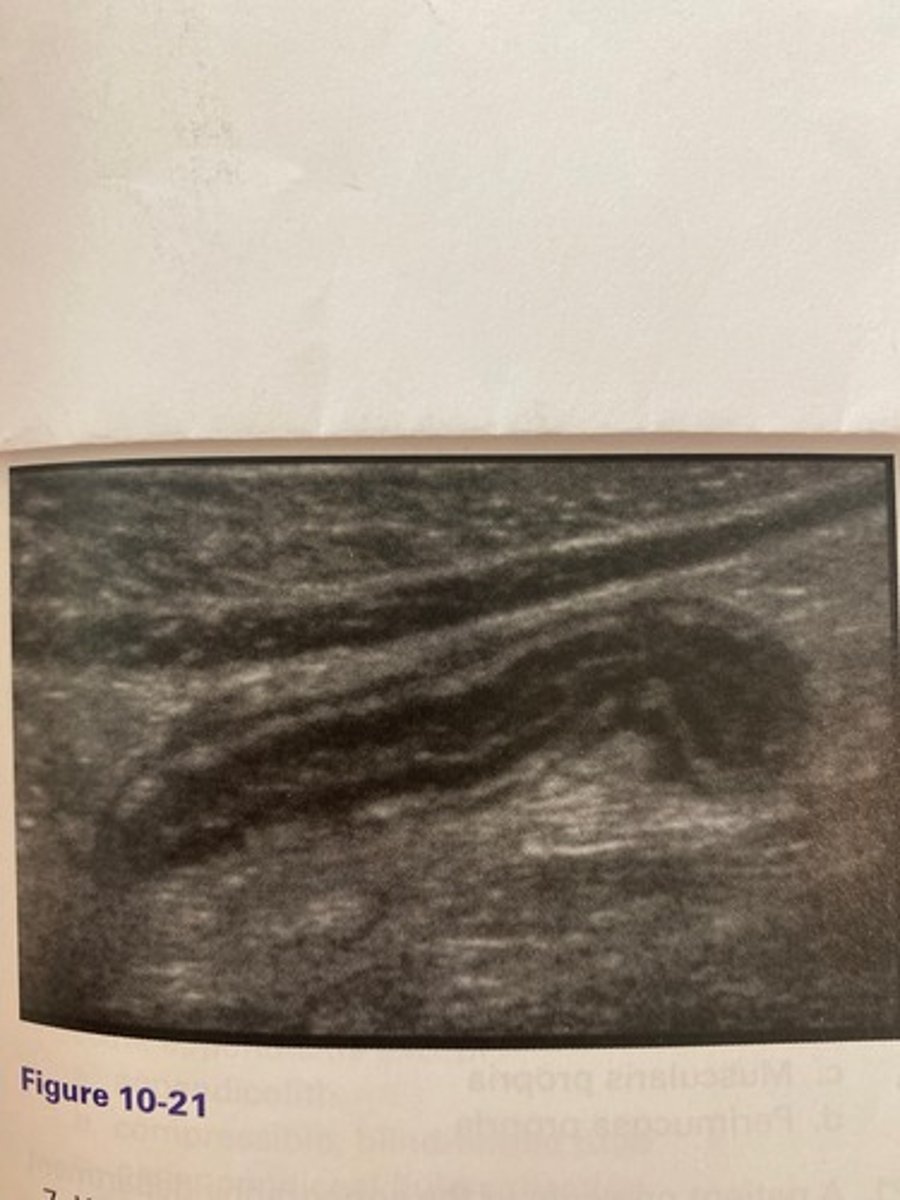

The patient in Figure 10-21 presented with right lower quadrant pain and nausea. The anteroposterior measurement of this structure in this image should not exceed:

a. 4 mm.

b. 3 mm.

c. 10 mm.

d. 6 mm.

b. Leukocytosis

Which of the following would be another common clinical finding for the patient in Figure 10-21?

a. Thyroid in the belly sign

c. Kernicterus

d. Hypernatremia

What is the thyroid in the belly sign?

a. Anechoic fluid surrounding an inflamed bowel segment

b. Hypochoic material adiacent to a distended pyloric stenosis

c. Enlargement of the distal colon in the presence of diverticulitis

d. Hyperechoic edematous connective tissue surrounding an inflamed appendix